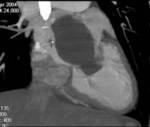

Methods: Twenty-two patients referred to our department with a suspected cardiac mass, previously detected by cardiac ultrasound, were evaluated by CT (12 patients) and MRI (4 patients). Six patients were examined by both modalities. In 2 cases of staging of a known primary neoplasm and one case of a suspected epicardiac lesion, positron emission tomography (PET-CT) was performed. The CT cardiac examinations were performed using a 16-slice multislice scanner with ECG gating. The MRI examination was performed on a 1.5 Tesla MRI scanner using an ECG-gated cardiac protocol and the PET-CT examination was performed on an integrated PET-CT four-slice scanner, using 370 mMBq of fluorodeoxyglucose.

Results: Twenty-two cardiac masses were successfully detected and their characteristics adequately delineated, including eight myxomas, one angiosarcoma, one ventricular lymphoma, one endocardiac metastasis, one epicardiac paraganglioma, and 10 cases of intracardiac thrombi.

Conclusion: CT and MRI are noninvasive imaging modalities which can delineate cardiac tumors and masses and provide essential information for adequate diagnosis, staging and treatment planning. Compared to cardiac ultrasound, CT and MRI are superior in preoperative planning.